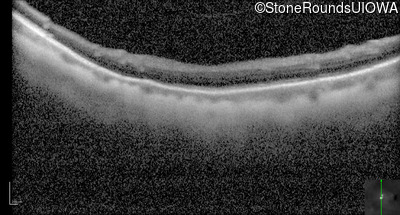

Optical Coherence Tomography - Right - 20/100 -1

Exemplar / OCT Stack

OCT Stack